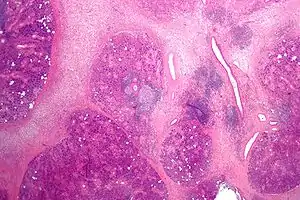

The gland is internally divided into lobules. Blood vessels and nerves enter the glands at the hilum and gradually branch out into the lobules.

Acini

Secretory cells are found in a group, or acinus (plural, acini). Each acinus is located at the terminal part of the gland connected to the ductal system, with many acini within each lobule of the gland. Each acinus consists of a single layer of cuboidal epithelial cells surrounding a lumen, a central opening where the saliva is deposited after being produced by the secretory cells. The three forms of acini are classified in terms of the type of epithelial cell present and the secretory product being produced: serous, mucoserous and mucous.[17][18]

Ducts

In the duct system, the lumina are formed by intercalated ducts, which in turn join to form striated ducts. These drain into ducts situated between the lobes of the gland (called interlobar ducts or secretory ducts). These are found on most major and minor glands (exception may be the sublingual gland).[17]